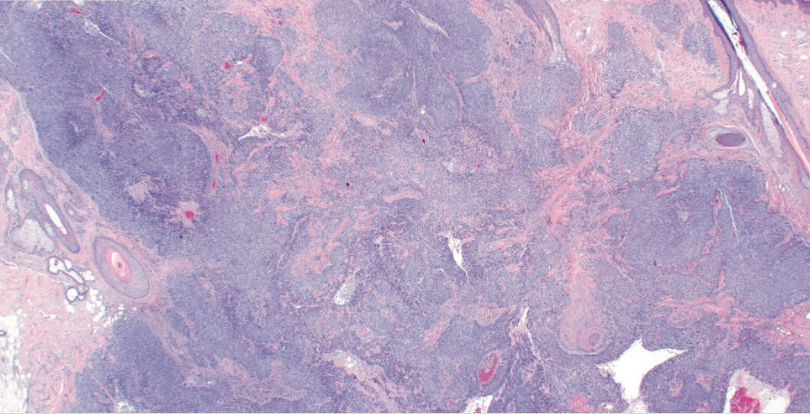

How the Emergence of Immunotherapy has Impacted Practice Patterns for Treatment and Management of Merkel Cell Carcinoma

A retrospective review identified that clinical practice patterns have changed from 2002 to 2020, with the use of immunotherapy increasing as chemotherapy and radiation therapy use has decreased for patients with Merkel cell carcinoma.

The adoption of immunotherapy for patients with Merkel cell carcinoma (MCC) has contributed to changing practice patterns at an institutional and national level, which match with emerging data regarding the optimal treatment of this disease, according to the results of a retrospective review published in the Annals of Surgical Oncology.